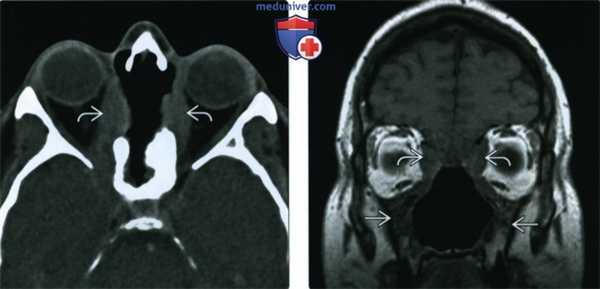

(Слева) При аксиальной КТ без КУ определяется деструкция верхней части носовой перегородки и глазничной пластинки с обеих сторон. В этом случае имеет место гранулематоз с распространением в обе орбиты.

(Справа) При корональной МРТ Т1ВИ у этого же пациента определяется нарушение нормальной анатомии носа и утолщение стенок верхнечелюстных пазух. Жировые пластинки между измененными мягкими тканями и внутренней прямой и верхней косой мышцами видны неотчетливо.

(Слева) На аксиальной КТ без КУ определяется деструкция верхних отделов носовой перегородки, перегородок между ячейками решетчатой кости, обеих глазничных пластинок (двухстстроннее поражение глазницы при гранулематозе).

(Справа) На корональной МРТ (Т1 ВИ) у этого же пациента определяется нарушение анатомии структур полости носа и утолщение стенок верхнечелюстных пазух. Жировые пластинки между патологически измененными мягкими тканями и медиальной прямой и верхней косой мышцами плохо различимы.